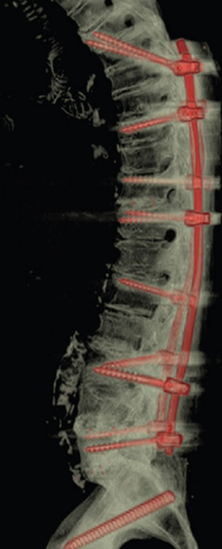

图12 CBT+TT+多棒固定

CBT+TT+多棒固定

从融合节段向活动节段未行过渡性手术,导致局部应力分布不均,局部应力过于集中,也是交界性问题的危险因素之一。

长节段固定时,融合区和活动区应适当行过渡性手术,可降低PJK发生的风险。

图13 长节段全椎弓根螺钉固定,局部应力过于集中